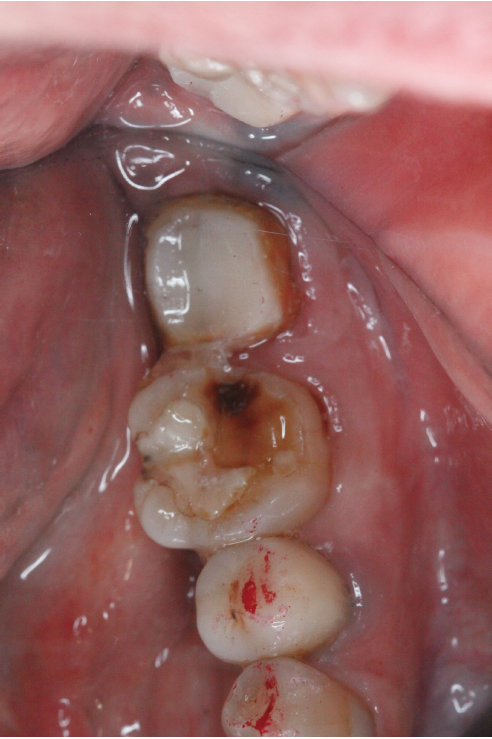

そしてこの再植と言う治療に入ると歯を一旦抜くことによって一時的に歯は弱まるのでしっかり休めなければなりません、期間はその歯の状態や個々の回復の差によりますが基本的には4ヶ月程休ませてあげます。その4ヶ月の間歯は噛ませることなくそっとしておくのですがその待っている間に『土台』を建てます。(写真3)この土台に関しては当会の会報誌でもまだ説明したことがないのでいずれ紹介しようと思っています。この土台の治療とは根っこの治療が終わった歯にするもので根っこに再度菌が入り込みにくくする、歯を割れにくくする、などの意味があります。